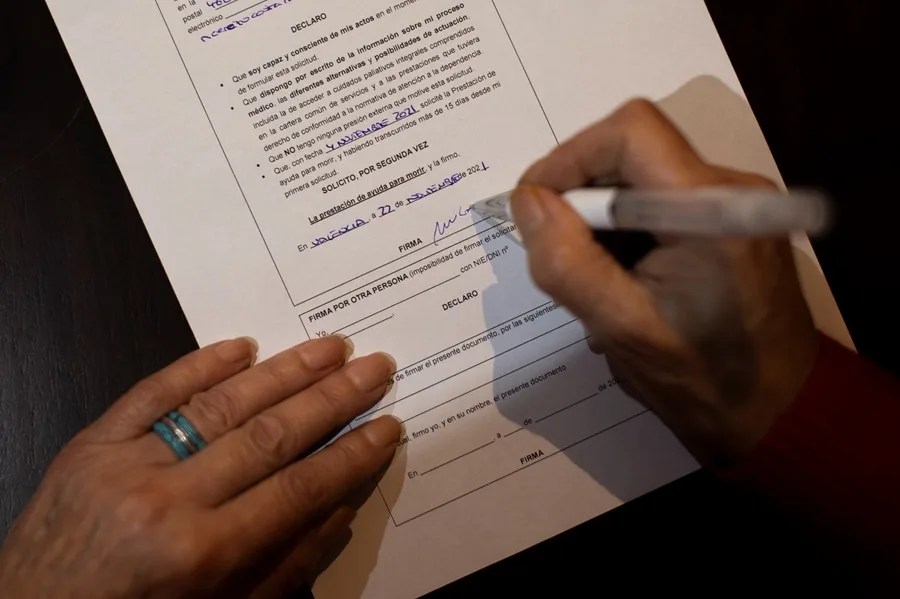

La joven Noelia Castillo recibe la eutanasia tras un largo periplo judicial

Noelia Castillo, una mujer de 25 años, falleció este jueves tras someterse a eutanasia en Sant Pere de Ribes, después de una batalla legal que duró más de un año y medio. La organización Abogados Cristianos, que ha defendido al padre de Noelia Castillo en sus apelaciones legales, ha comunicado que la eutanasia se realizó…

La justicia descarta de nuevo frenar la eutanasia de Noelia, horas antes de practicarse

La justicia ha decidido no suspender la eutanasia de Noelia, al rechazar las medidas cautelares que la fundación Abogados Cristianos presentó. Esta organización ha defendido al padre de Noelia en su lucha legal para evitar que se lleve a cabo su muerte asistida. Ha pedido medidas cautelares por tercera ocasión ante el juzgado de instrucción…